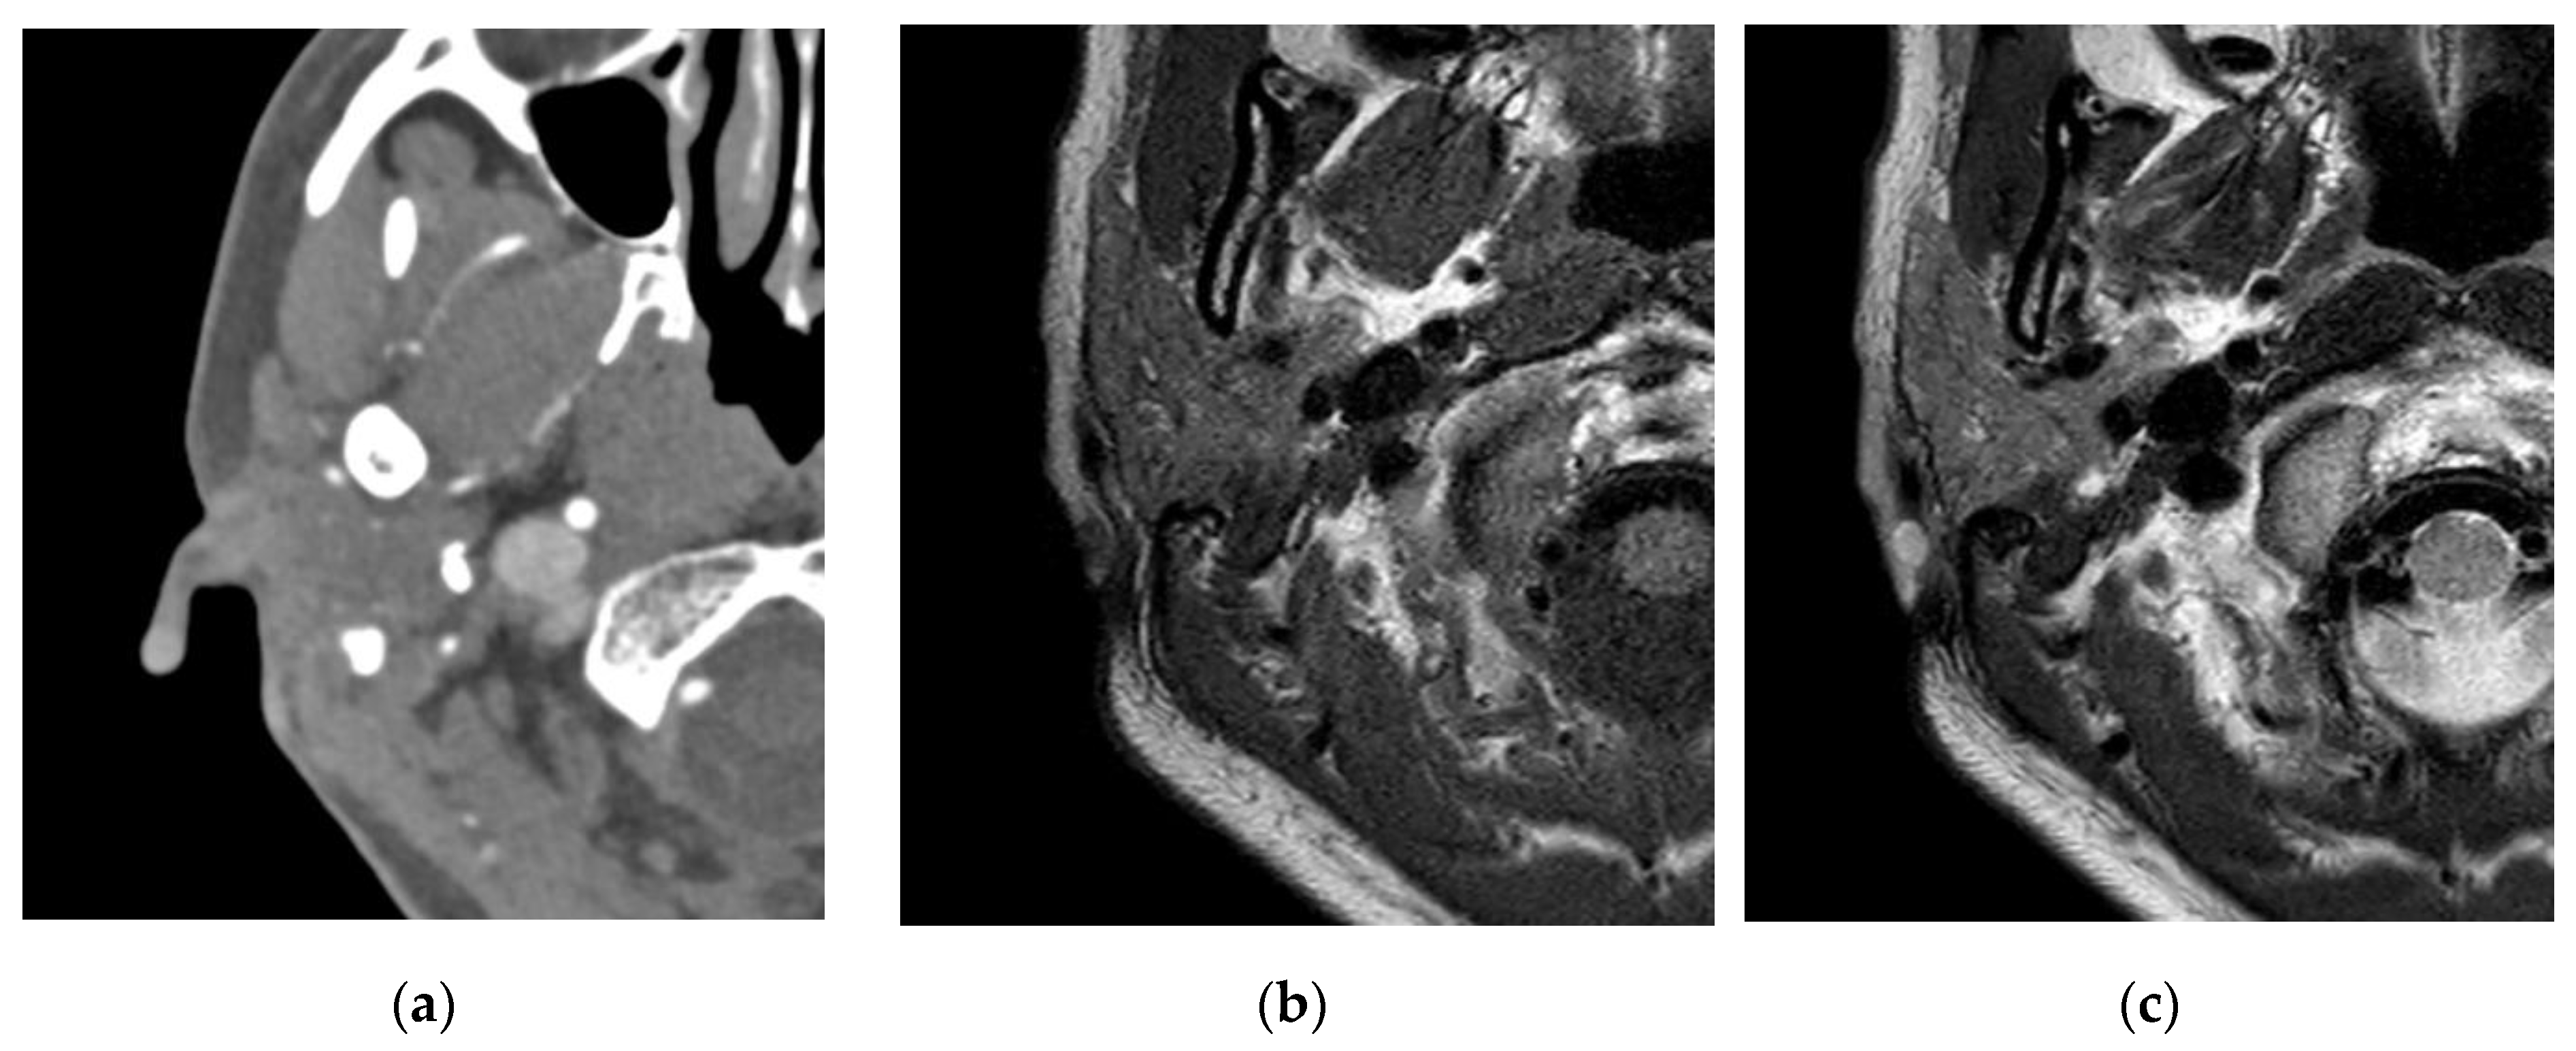

Figure 2. On brain computed angiography, an enhanced mass about 0.5 × 0.5 cm in size with soft tissue density was revealed at the helix of the right auricle. (a) Through neck magnetic resonance imaging (MRI), the mass at the helix of the right auricle was revealed with low signal intensity in T1-weighted images (b) and high signal intensity in T2-weighted images. (c) With suspicion of vascular tumor, surgical excision was planned upon patient request.

Venous malformations appear as isointense in T1-weighted images and hyperintense in T2-weighted images, and it is enhanced with contrast [1]. T2-weighted images from MRI can be used to differentiate vascular lesions. Hemangioma and venous malformations show a more intense enhancement than arteriovenous and lymphatic malformations. Venous and lymphatic malformations show a high signal intensity in T2-weighted images, whereas hemangioma and arteriovenous malformations show an intermediate signal intensity in T2-weighted images [10].